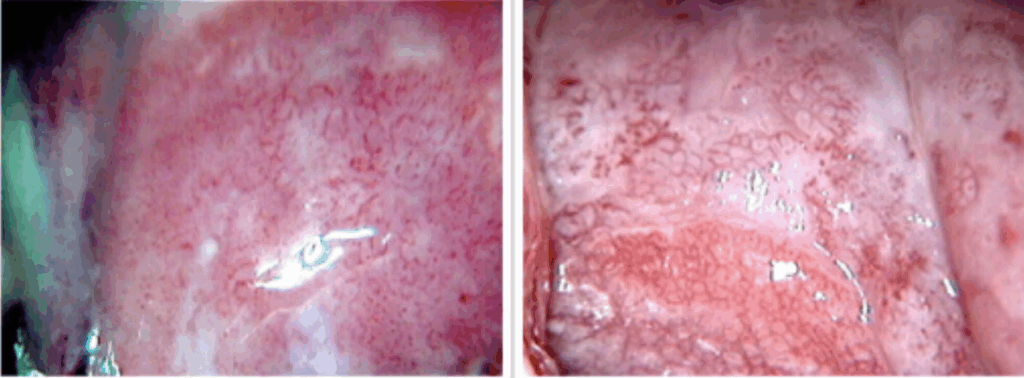

É o exame do colo do útero com um microscópio (colposcópio) após a aplicação de reagentes para realçar áreas suspeitas.

- Limpeza com Solução Salina: Para remover o muco e observar a vascularização inicial (vasos atípicos, pontilhados, mosaicos).

- Aplicação de Ácido Acético (3-5%): Coagula as proteínas. Células com alta atividade de replicação (lesões) ficam com um aspecto branco (epitélio acetobranco).

- Teste de Schiller (Aplicação de Lugol): O iodo cora o glicogênio das células normais de marrom. Células displásicas, pobres em glicogênio, não se coram e ficam amareladas (iodo-negativas ou Schiller-positivo), indicando o local ideal para a biópsia.

- Grau 1 (Menores): Compatíveis com ASC-US/LSIL. Incluem epitélio acetobranco tênue, borda irregular e mosaico ou pontilhado fino.

- Grau 2 (Maiores): Sugerem lesões de alto grau. Incluem epitélio acetobranco denso, mosaico grosseiro e atipia vascular.

- Junção Escamocolunar (JEC): A visualização completa da JEC é crucial. Se a JEC não é totalmente visível (localizada dentro do canal), a colposcopia é considerada insatisfatória.